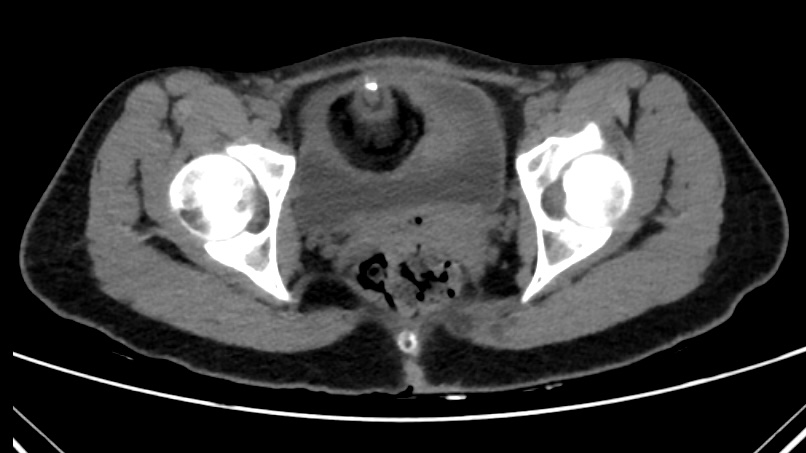

La TC abdominal mostró cuatro lesiones anexiales bien delimitadas, con predominio de contenido graso y nódulos murales calcificados, altamente compatibles con teratomas ováricos bilaterales, sin líquido libre en ese momento.